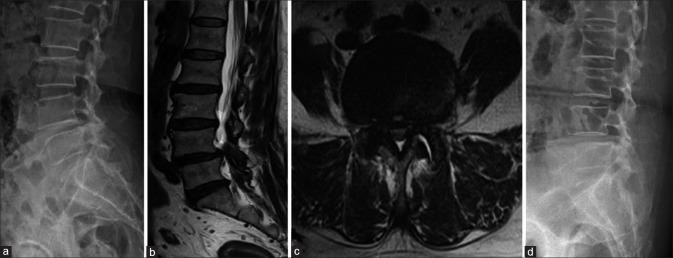

For Grade I degenerative lumbar spondylolisthesis (DLS), both decompression alone and decompression with fusion are effective surgical treatments. Which of the two techniques is superior is still under debate. The purpose of this study was to compare clinical outcomes after decompression alone versus decompression with fusion for Grade I DLS.

139 patients who underwent surgery for Grade I DLS at L4-L5 were prospectively enrolled. Decompression alone was used to treat 74 patients, and decompression with fusion was used to treat 65 patients. Six patients in the first group and four patients in the second group were lost during the 2-year followup. Demographic data were recorded. Operation time, perioperative blood loss, total blood transfusion volume, and length of hospital stay were compared between the two groups. Back pain and functional outcomes were evaluated using the visual analog scale (VAS) and the Oswestry Disability Index (ODI), respectively.

Baseline demographic data were not different between the two groups. Operation time, blood loss, total blood transfusion volume, and length of hospital stay were all significantly greater in the fusion group than in the decompression group. This would be expected because fusion is the more invasive procedure. VAS scores were not different up until 6 months postoperatively. Twelve months after surgery, however, VAS scores were significantly lower in the fusion group. The same results were shown in terms of ODI. Although ODI decreased in both groups over time, the fusion group showed better functional outcomes than did the decompression group.

Although both decompression alone and decompression with fusion improved functional outcomes for Grade I DLS, fusion surgery resulted in better results compared to decompression alone. Therefore, fusion should be considered as the treatment of choice for Grade I DLS.